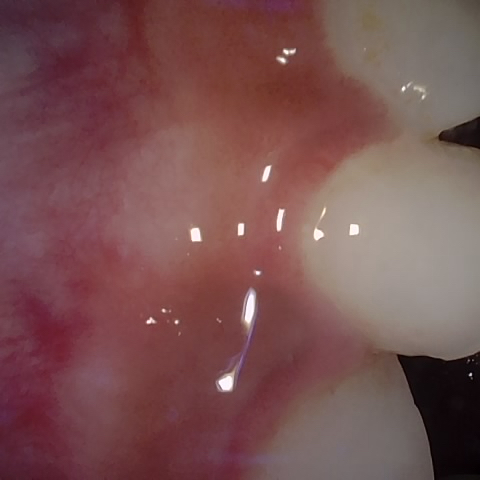

Image 909 / 1103

NHD39174

Annotated as "Bad"

Original Image Rendering Image